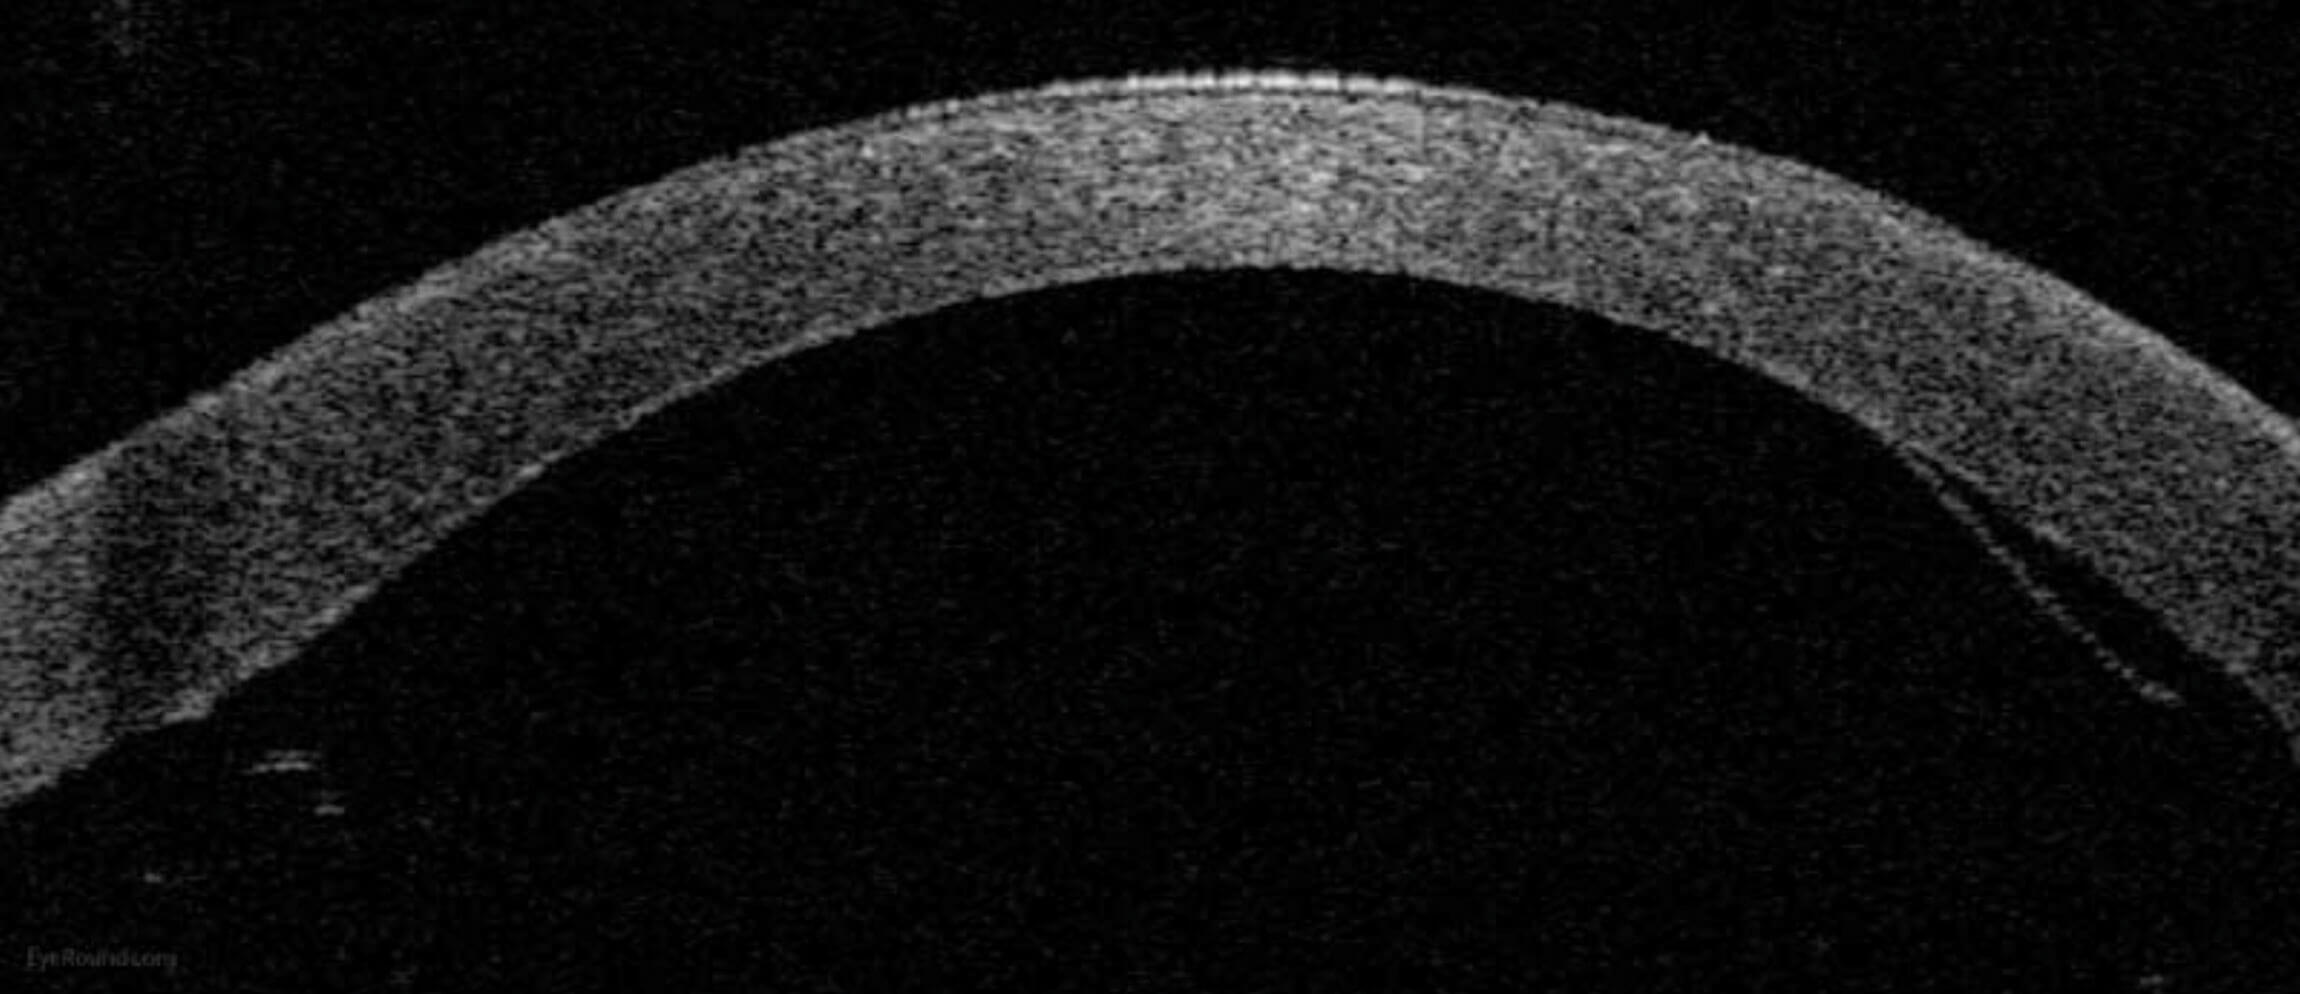

Figure 1: Anterior segment optical coherence tomography demonstrating an attached

DSAEK graft one day after surgery. © EyeRounds.org University of Iowa USA.